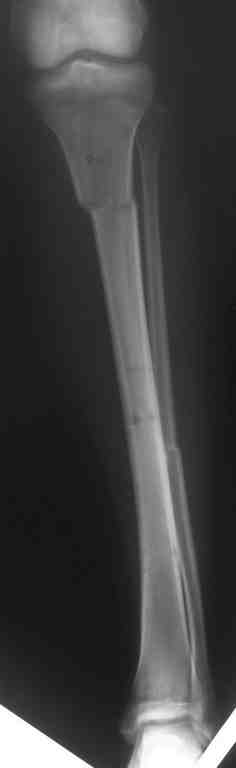

Выше приведены рентгенограммы 13-летнего подростка, страдающего от огнестрельного многооскольчатого перелома дистальной трети бедра. AO наружный фиксатор наложенный в день травмы не дал приемлемой редукции. Через три недели после перелома аппарат Илизарова был наложен без попытки одномоментной репозиции на операционном столе. There are X-Rays of a thirteen year old boy with a comminuted distal femur fracture secondary to a gunshot wound, initially treated with an AO external fixator. The alignment was unacceptable and an Ilizarov external fixator was applied three weeks after the injury. No attempt of definitive reduction was made during the surgery.

Гексаподная приставки наложена на 10 дней и приемлемая редукция была получена. The Hexapod set was applied for ten days and acceptable reduction was received.

По окончанию редукции Гексаподный сет был снят и дальнейшее ведение больного проходило в стандартном режиме аппарата Илизарова. Хороший анатомо-функциональный результат был получен. When reduction was finished, the Hexapod set was removed and further management has been continued by standard Ilizarov regime. Good anatomic and functional results were achieved.